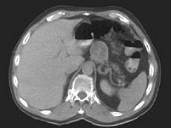

问题 50岁男性患无功能分化好的胰岛细胞瘤伴有肝多发12cm的转移结节,应()

选项 A.观察,目前不必要进行治疗 B.开腹手术切除大块肿瘤 C.化疗,选择阿霉素和链霉素 D.化疗,选择链霉素加氟尿嘧啶 E.化疗,选择顺铂加VP-16

答案 A